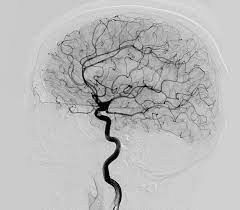

La angiografía cerebral utiliza un catéter, la guía por rayos X y una inyección de material de contraste para examinar vasos sanguíneos en el cerebro para identificar anormalidades tales como aneurismas y enfermedades como la aterosclerosis (placa). El uso del catéter hace posible la combinación del diagnóstico y tratamiento en un sólo procedimiento. La angiografía cerebral produce imágenes muy detalladas, claras y precisas de los vasos sanguíneos del cerebro, y puede eliminar la necesidad de una cirugía.